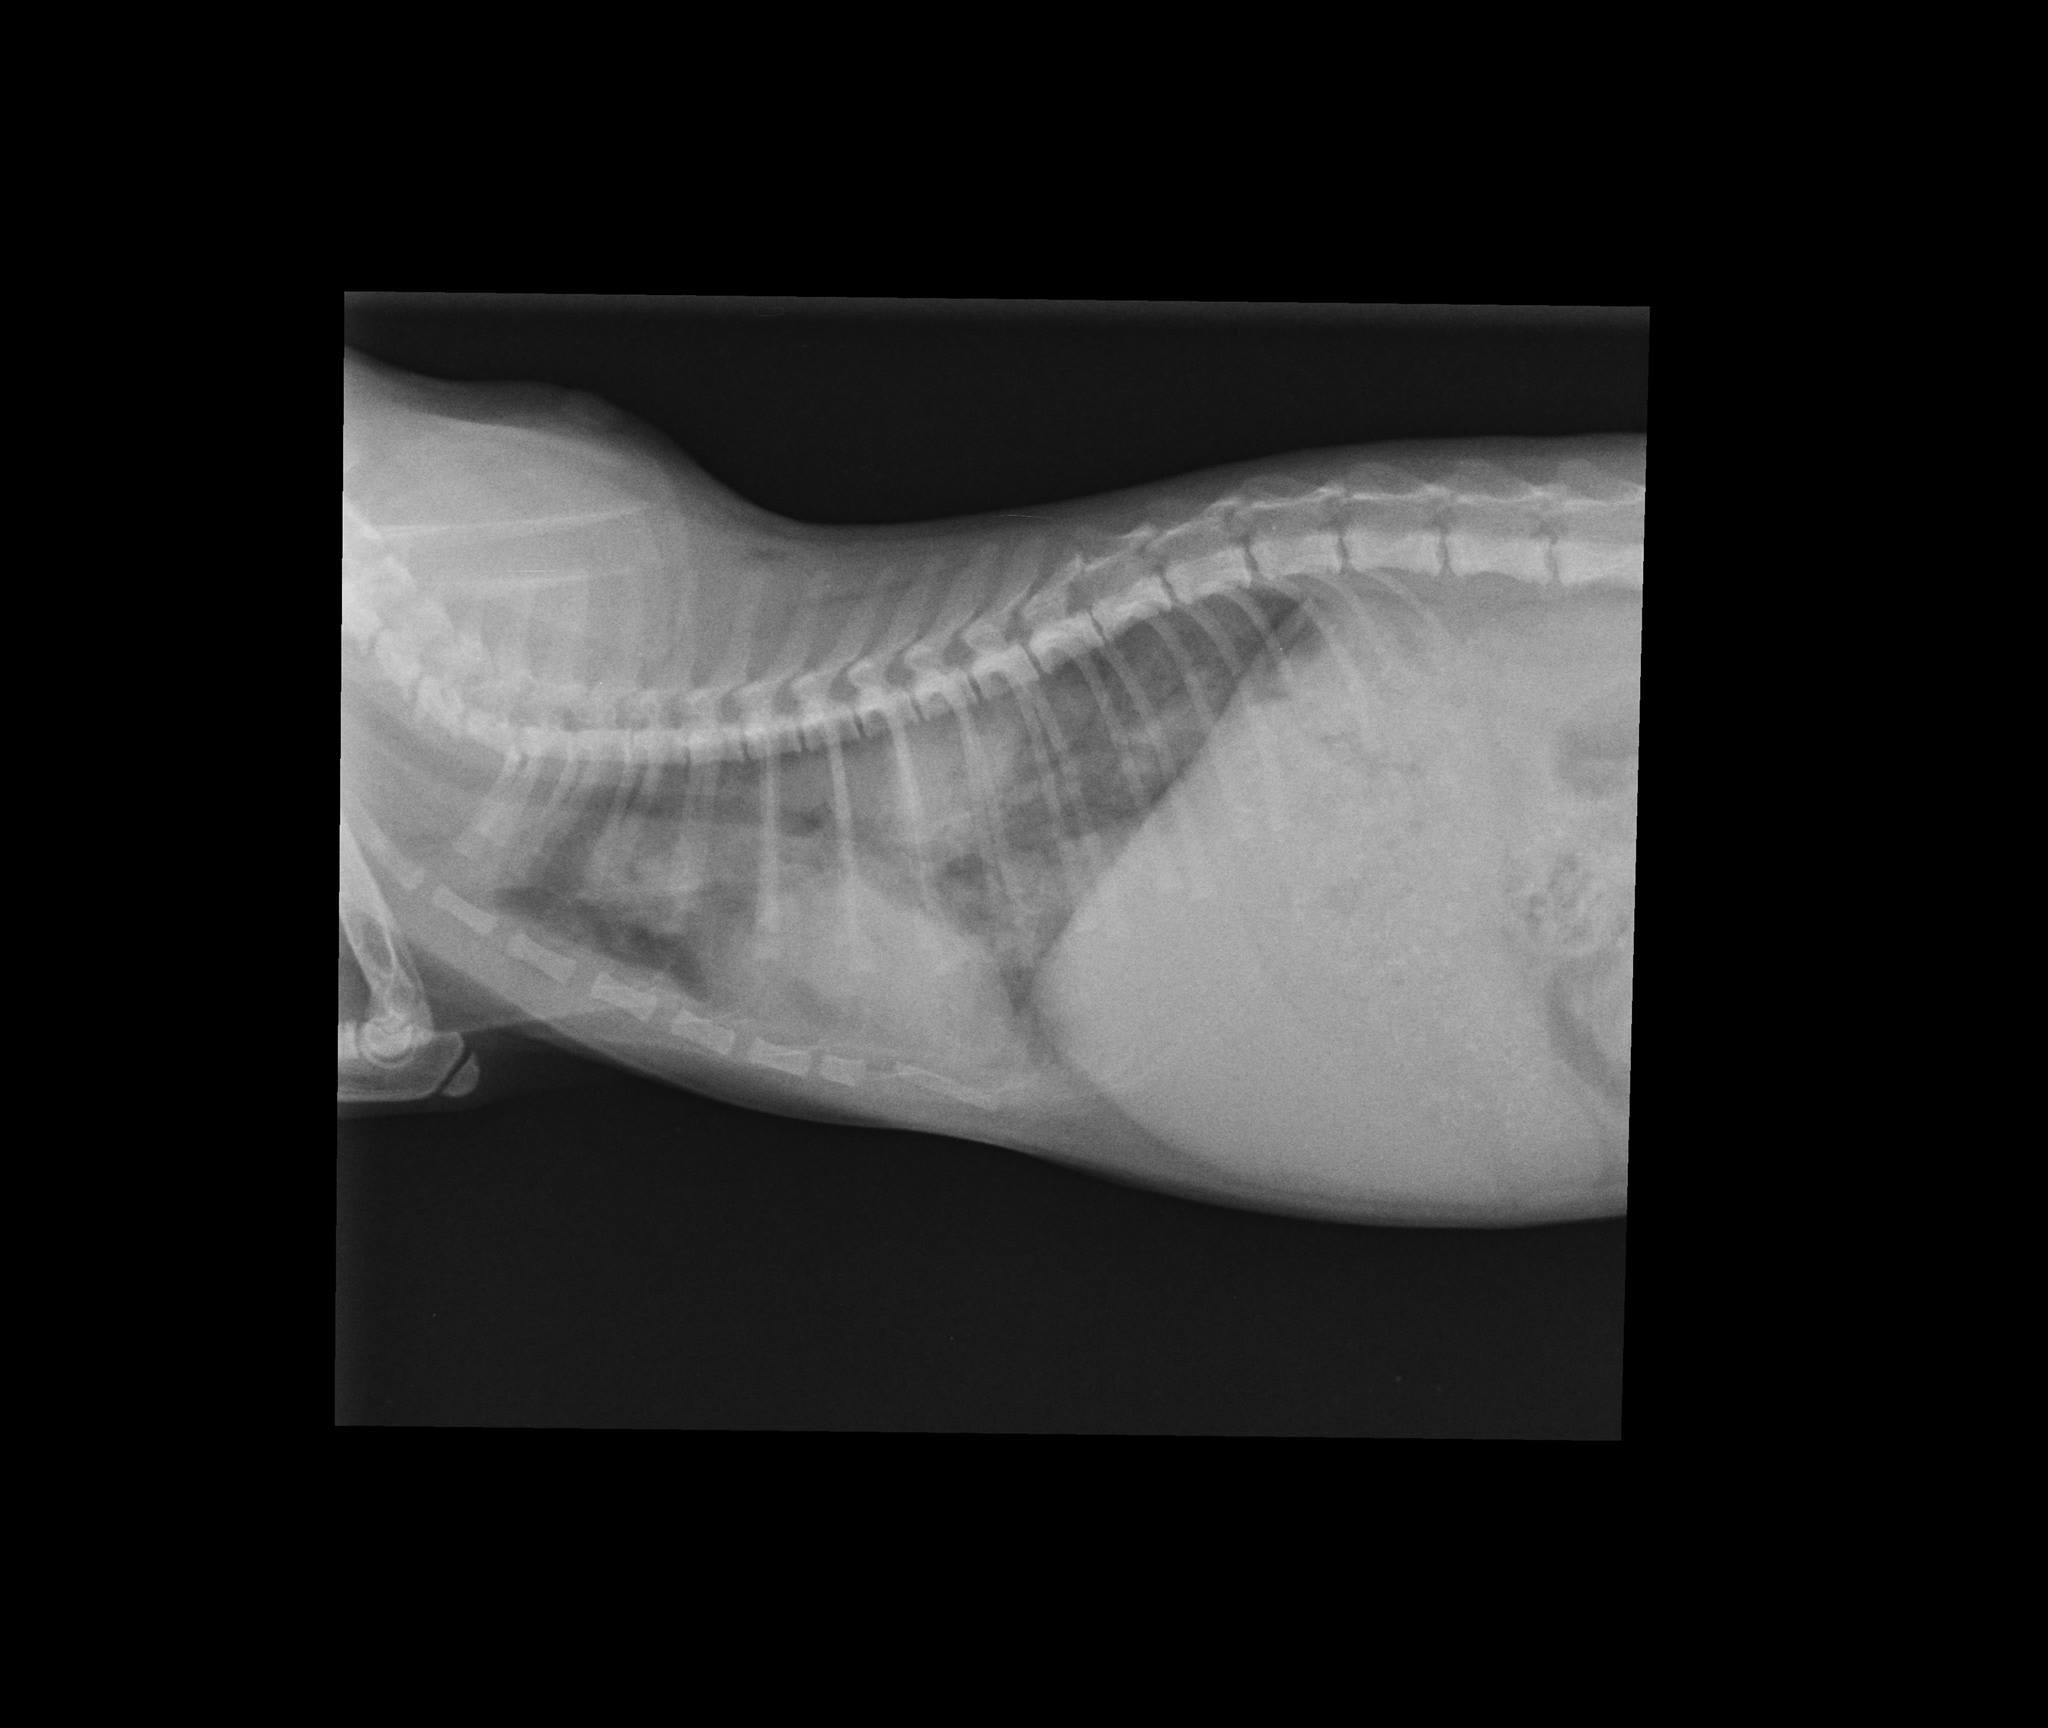

Hello, I have a question regarding my rescue kitten. He is around 5 months old. I found him 3-4 weeks ago, on the verge of death. He was severely dehydrated, had diarrhea, fever and was unresponsive. After a week of antibiotics, he got better. He runs around, plays, but he breaths kind of heavily. Also, he has some episodes of dry heaving. Our vet recommended we do a thoracic radiography. Could you please tell me if you see anything wrong? Thank you so much. Kind regards, Andreea N.

I'm sorry to hear that you are having trouble with Loki. It is always best to interpret X-rays along with physical exam findings and not just going by the picture alone. It is best to have your veterinarian give you their opinion based on the X-ray and the exam findings, but -in my opinion- this is not a normal appearing chest X-ray for a kitten. The white densities visible in multiple lung lobes may represent consolidation which may indicate pneumonia. This may be due to a bacterial infection or fungal infection or lung parasite. I would definitely recommend further discussion with your veterinarian to start a new course if treatment- whether that is another antibiotic or another type of medication would be based on your vet's recommendation.